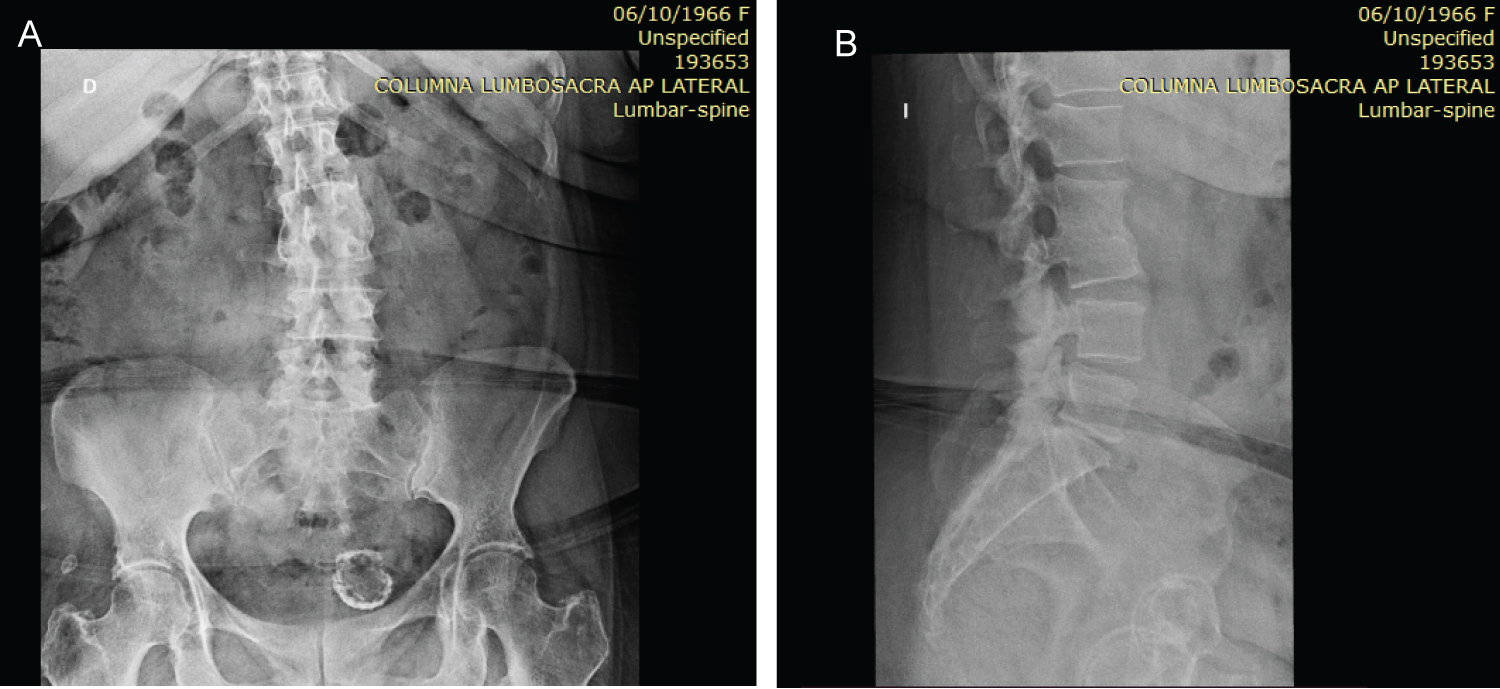

Radiological images are essential to establish the diagnosis by identifying what stage of disease progression the patient is in (trophic or hypertrophic stage), in the case of our patient he is in a hypertrophy stage (Figure 1), in which we can observe destruction and erosion of the vertebral bodies as well as disc degeneration and the presence of atrophic osteophytosis at the L2-L3 level [1,7].

Figure 1: (A,B) AP and Lateral X-ray of the lumbar spine showing complete vertebral fusion at the level of L2-L3. The process can be observed already in the consolidation phase, without signs of instability. View Figure 1